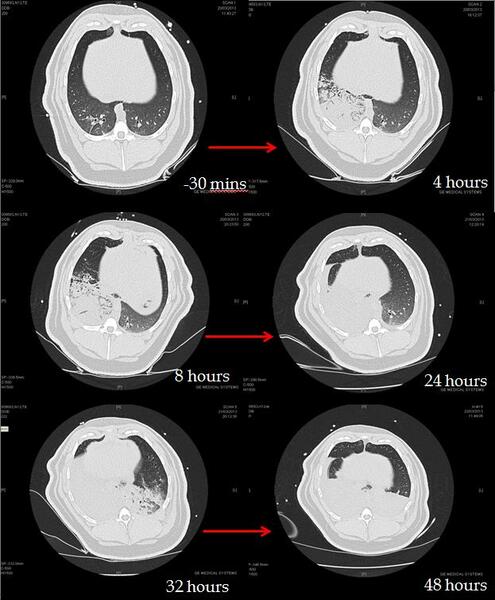

CT analysis of an OP and GJ pig lungs show the direct and indirect effects of aspiration over time (figure 2).

Figure 2: Time series CT lung scans taken from one pig at -30 minutes (before aspiration) to 48 hours after instillation of 0.5mls/kg mixture of OP and gastric juice in the right lung at time 0 hours. Over time, the right lung becomes more consolidated and at 32 hours the left lung also starts to show an indirect injury. At 48 hours bilateral posterior consolidation and fluid in the fissures are apparent.

Mixtures of OP and GJ and GJ alone when instilled into the right lung seem to create the worst lung injuries in comparison to solvent and GJ and control animals.